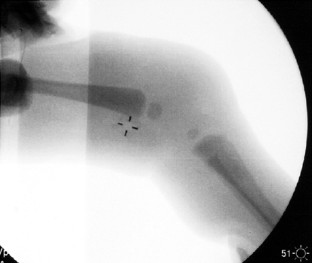

Neonatal physeal fracture of the distal femur is often difficult to diagnose. Timely and accurate diagnosis and appropriate therapy are critical in order to avoid permanent morbidity and dysfunction of the affected limb. We describe an infant in whom closed reduction and pinning were required in order to assure a good outcome.